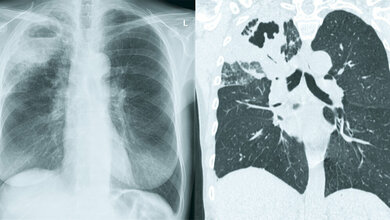

Eine Früherkennung der Infektion durch das Bakterium Mycobacterium tuberculosis (Mtb) ist durch die Nutzung humaner Macrophagen (Fresszellen des Immunsystems) als quasi Wirt zur Vermehrung des Mtb stark erschwert. Aufgrund dieses „Versteckspiels“ des Mtb in den menschlichen Macrophagen greifen übliche Methoden der Diagnostik erst nach dem Kollaps der Macrophagen, man spricht dann von der „offenen Tuberkulose“. Mtb kann durch gängige Antibiotika, die über lange Zeiträume verabreicht werden, behandelt werden, allerdings fördert die wiederholte Exposition von Mycobacterium tuberculosis (Mtb) mit gängigen Antibiotika die Entwicklung multiresistenter und extensiv arzneimittelresistenter Stämme.